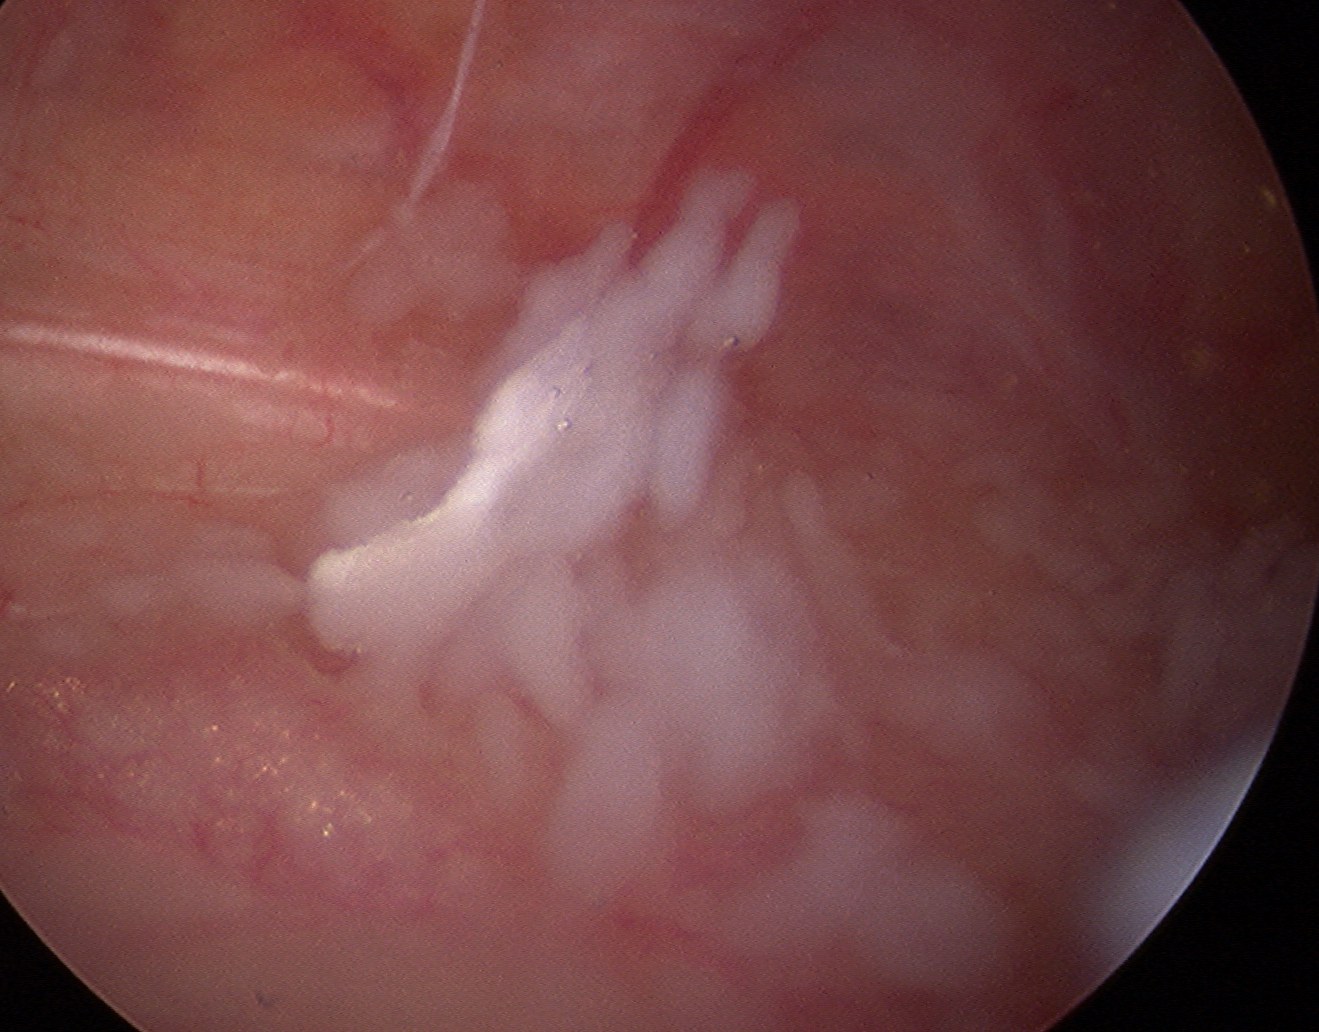

Arthroscopy

Synovial proliferation

- localised or generalised

- can see cartilage growing from synovium

Multiple loose bodies +++